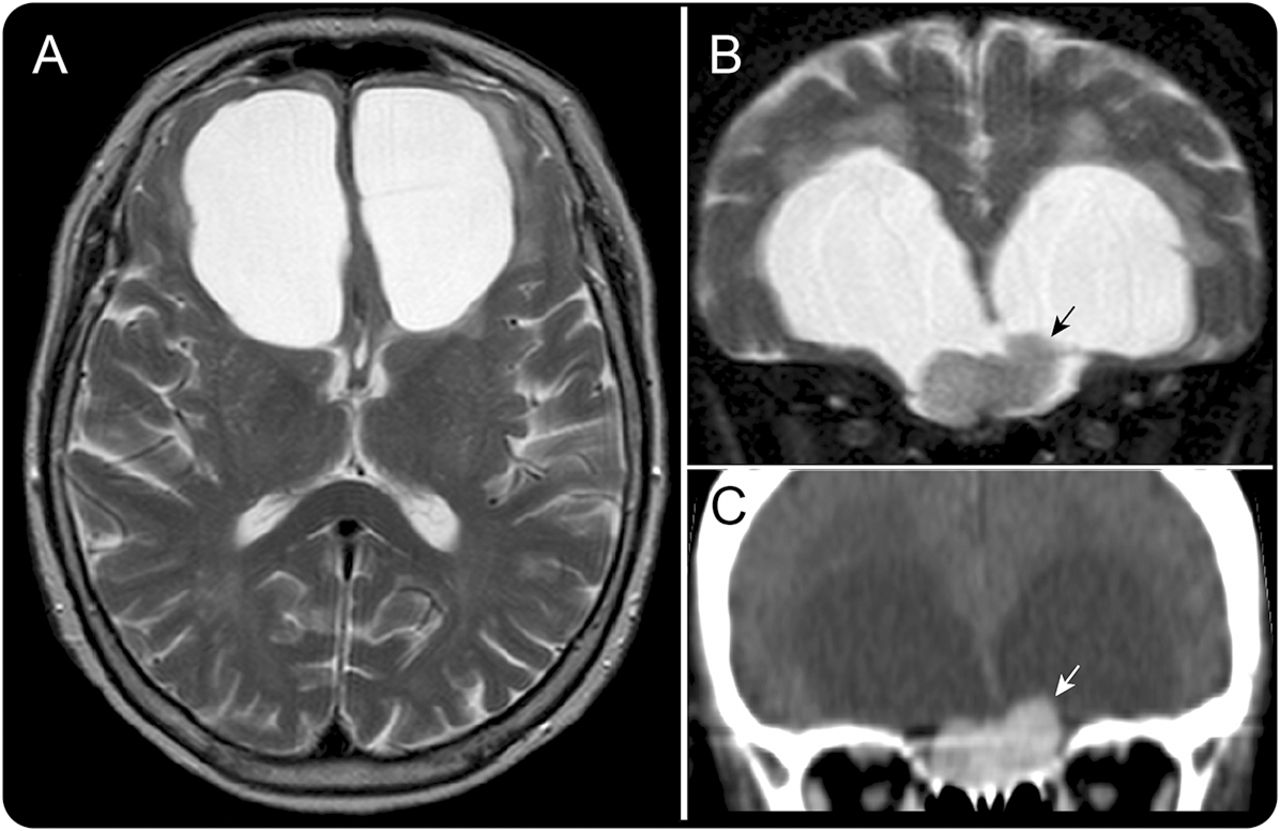

一个73岁的女人有进步的冷漠,健忘,步态障碍为6个月。神经系统检查显示、恶声恶气,记忆障碍和广泛的步态。41 MRI表现是因为钆过敏。MRI和超声造影CT扫描显示对称双边额囊肿(图1一个)和一个前颅底结节(图1中,B和C)。手术证实了脑膜瘤起源于鸡冠(图2一个)。她的症状改善术后囊肿严重萎缩(图2 b)。

图1

对称双边额囊肿和肿瘤的MRI和CT

(一)轴向和(B)冠状t2加权MRI显示大型对称双边额囊肿和isointense结节筛状板(箭头所指)。(C)对比增强CT扫描显示结节是同质的增强(箭头所指)。鉴别诊断包括脑膜瘤,鼻腔神经胶质瘤和血管外皮细胞瘤。